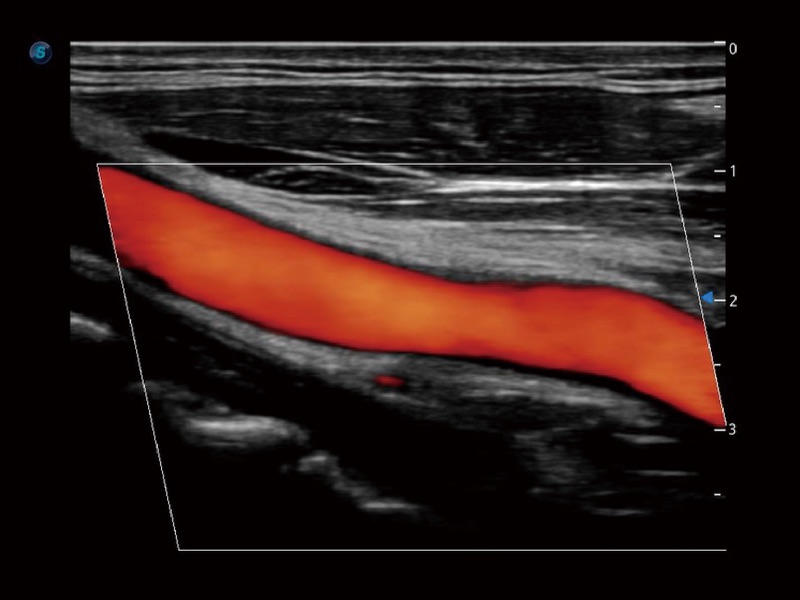

高分辨率血流成像技术提高了对低速血流信号的检测能力。在提高空间分辨率的同时,也克服了血流外溢现象,为用户提供更加真实的血流动力学信息。

血管内中膜的厚度值是预测心血管疾病风险的重要指标,Auto IMT可以实现血管近场和远场内中膜厚度的自动测量,为临床提供快捷有效的诊断工具。

心血管应用